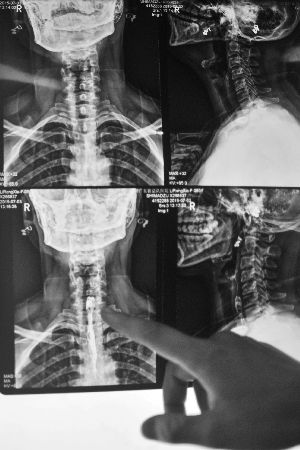

從X光片可以看見黎女士喉嚨中的異物。

主治醫生李靖稱,患者入院時,由于喉嚨紅腫嚴重,初步檢查無法判斷異物位置,為安全起見,先為其做消腫治療。“后來才知道是粽子里的棗核卡里面了,現在要等復查結果。如果異物不能順下去,就要考慮手術治療了。”黎女士稱,目前她喉嚨的疼痛感減弱不少,但喝水、吃東西還是會有明顯的不適。